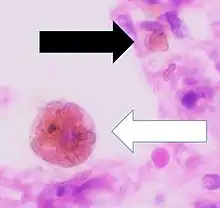

| Chronic pulmonary congestion | Siderophages | Brown-golden and refractile.[5] | Alveoli[6] |

|

|

Siderophage (black arrow), and interstitium with edema, hemosiderin deposition (black arrow) and collagenous thickening, indicating heart failure. |